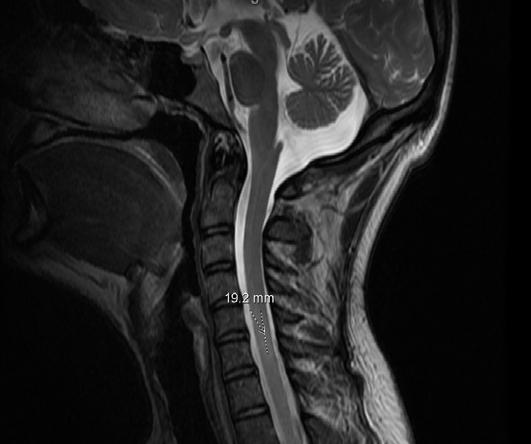

Imágenes:

Figura 1: Resonancia magnética cerebral con y sin contraste intravenoso. Áreas periventriculares de aumento de señal FLAIR con área focal de aumento de señal FLAIR en la cápsula interna derecha. También se observa un aumento de señal FLAIR en el pedúnculo cerebral derecho. Hallazgos consistentes con esclerosis múltiple.

Figura 2: Resonancia magnética de la columna cervical sin y con contraste intravenoso. Aumento intermitente en la intensidad de la señal T2 en el lado izquierdo de la médula posterior a C5 y C6, midiendo aproximadamente 1.9 cm en la dimensión craniocaudal. Consistente con enfermedad desmielinizante.